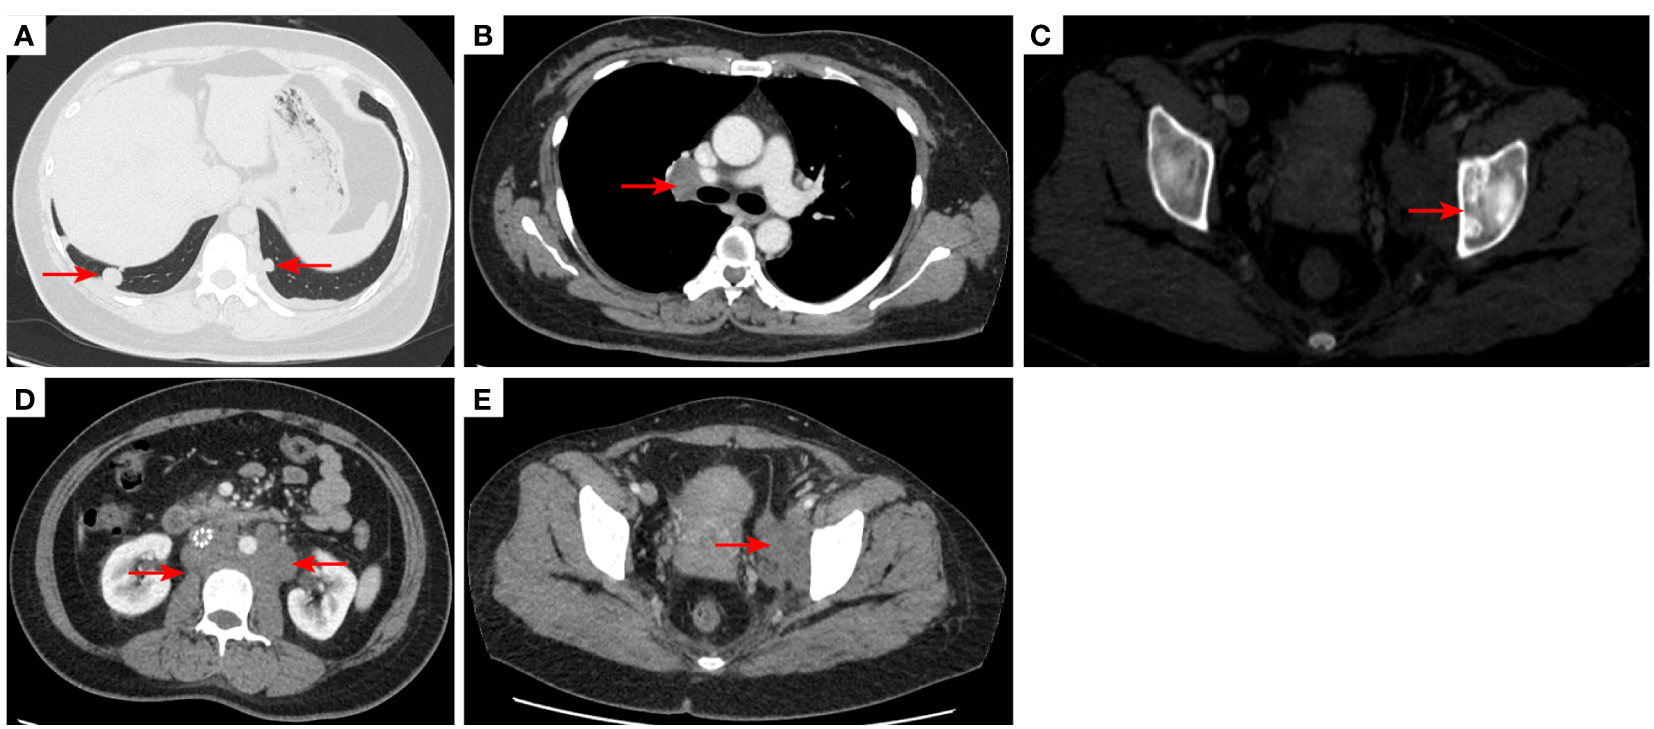

Figure 5

2020–12-22 CT scan: The right lower lobe of the lung metastatic tumor reappeared [red arrow, (A)] and the long diameter was 0.91 cm short diameter of right hilar lymph node was 1.66 cm [red arrow, (B)]; Left acetabular metastases [red arrow, (C)]. the short diameter of retroperitoneal lymph nodes was 1.66 cm, and the short diameter of left pelvic lymph nodes was 3.45 cm [red arrow, (D, E)]. The efficacy was PD. PD, progressive disease.